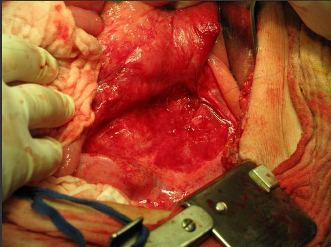

Operačná liečba

- Laparotomickým prístupom

- Laparoskopickým prístupom

- Verifikovať miesto úniku lymfy lymfografiou – Patent blue

- Sutúra

Sachs P.B.: AJR 1991, 157, 703-705